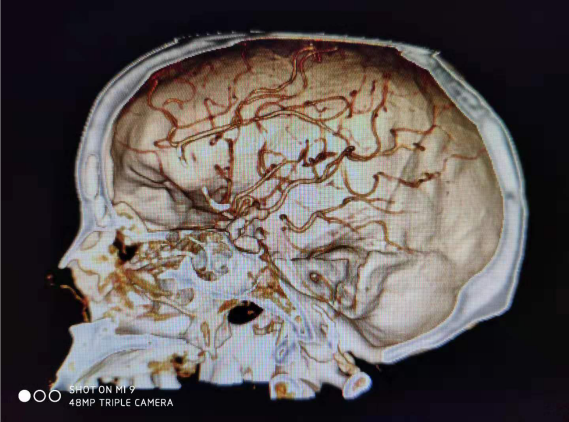

病例一:患者女性,49岁,因突发意识不清2小时,伴喷射性呕吐,大汗、四肢抽搐,就诊于本院神经外科接受治疗。积极完善相关检查,患者处浅昏迷,格拉斯评分7分,CT示:左侧额颞叶脑出血,量约33ml,并急诊行CTA(血管造影)示:左侧大脑中动脉M2段动脉瘤。急诊行“颅内血肿清除术+颅内动脉瘤夹闭+去骨瓣减压”,手术顺利,目前患者治愈出院。

病例二:患者老年女性,以突发头痛收入我科,头颅CT提示:蛛网膜下腔出血,头颅CTA提示:颅内动脉瘤。急诊行脑血管造影及动脉瘤栓塞,术后患者恢复理想,已治愈出院。